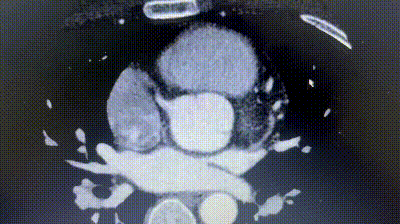

2. Coronary CTA revealed an anomalous origin of the left circumflex artery (LCX) from the right coronary sinus, with a course between the aorta and left atrium.

3. The distance between the ASD and the aberrant LCX was only about 6 mm.